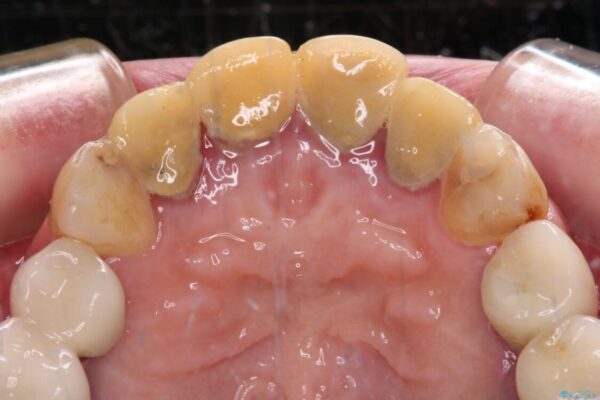

治療前

• 仮歯のまま放置した前歯 オールセラミッククラウンで自然な前歯に 治療前画像

仮歯が不適合で歯肉が腫脹していたため、しっかりと調整した新しい仮歯にして腫れを改善した上で、オールセラミッククラウンにて補綴することとしました。